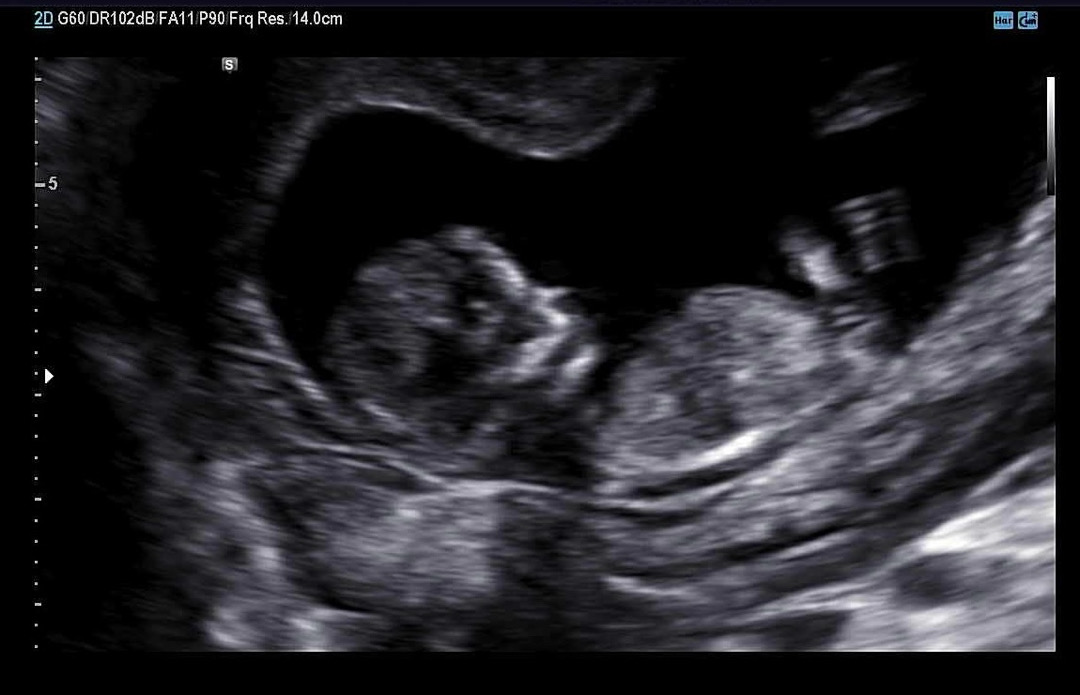

11주6일 각도법 봐주세용🫶

아들일까요 ? 딸일까요 ? ㅎㅎ